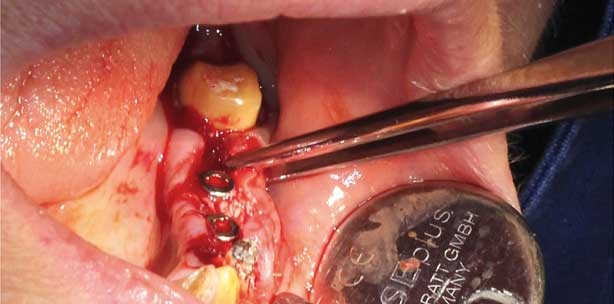

Nach Implantatinsertion darf die vestibuläre Knochenlamelle die Stärke von 1mm nicht unterschreiten. Die von Grunder, Gracis und Capelli 2005 angegebenen Abstände zwischen Zahn und Implantat von 1, besser 2 mm und zwischen zwei Implantaten von 3, besser 5 mm, müssen ebenfalls beachtet werden. Nach der Implantation wurde die Augmentation durchgeführt. Das Bio-Oss-Granulat wurde in der Körnung 1–2 mm gewählt und kann zusätzlich mit Eigenknochen und/oder Eigenblut vermengt werden. Eine ausreichend hohe Standzeit, verbunden mit einer langsamen Resorption durch Osteoklasten, führt zu einem kontrollierten Knochenum- und Knochenaufbau (Abb. 4–6). Die Bio-Gide-Membran wird zeltartig über das Augmentat gestülpt. Im Anschluss werden die Wundflächen speicheldicht, spannungsfrei und passiv mit einer Naht der Stärke 4-0 vernäht. Nach erfolgter Heilung per priman kann die Naht nach sieben Tagen entfernt werden (Abb. 7 und 8). In diesem Fall erfolgte nach vier Monaten die Freilegung und nach weiteren vier Wochen die Vestibulumplastik. Beide Eingriffe wurden in diesem Fall mit einem Diodenlaser (810 nm) durchgeführt. Diese Schritte sind natürlich auch mit dem Skalpell durchführbar. Die Vorteile des Lasers im Vergleich zur Skalpelltechnik sind die verkürzte Behandlungsdauer mit einer guten Wundheilung, die fehlende Naht, kaum auftretende Schmerzen und, darauf aufbauend, eine gute Patientencompliance. Nachdem das Weichgewebe einem ansprechenden Emergenzprofil gleicht, wurde zwei Wochen nach Freilegung mit der Abdrucknahme die prothetische Phase eingeleitet. Zusammen mit dem Zahntechniker wird die Art des Implantataufbaus ausgewählt (Abb. 9). Die Restauration wird nach entsprechender Gerüsteinprobe und Bissregistrierung dann provisorisch eingegliedert.